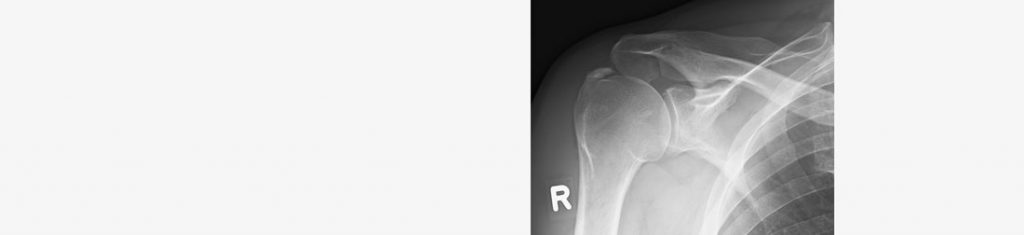

Wenn der Oberarmkopf aus der Pfanne herausspringt, spricht man von einer Schulterluxation. Dies passiert häufig bei Fahrradstürzen oder beim Betreiben von Kontaktsportarten. Doch kann es auch bei angeborener Fehlanlage bei Alltagsbewegungen zur Schulterluxation kommen.

Zum Vermeiden wiederholter Luxationen ist häufig die Rekonstruktion der Gelenkkapsel erforderlich. In der Regel ist diese Operation arthroskopisch durchführbar. Nach der Operation ist die Schulter für 6 Wochen nicht voll beweglich. Nach intensiver Physiotherapie wird die Arbeitsfähigkeit je nach beruflicher Belastung zwischen der 6. und 10. Woche erreicht.